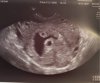

Witajcie kochane,

ja wczoraj byłam na pierwszym USG

i muszę się pochwalić na ekranie widać dwa zarodeczki ❤ ❤

Bardzo się cieszę i w ogóle mnie to nie martwi, mamy trochę bliźniaków w rodzinie i nawet trojaczki, wiec nic strasznego. To moja czwarta ciąża wiec będę miała teraz pięcioro dzieci. Jak dla mnie bosko :D:oo_O:D

Załączniki

• WhatsApp Image 2020-11-02 at 11.23.43.jpeg

WhatsApp Image 2020-11-02 at 11.23.43.jpeg

140,5 KB · Wyświetleń: 113